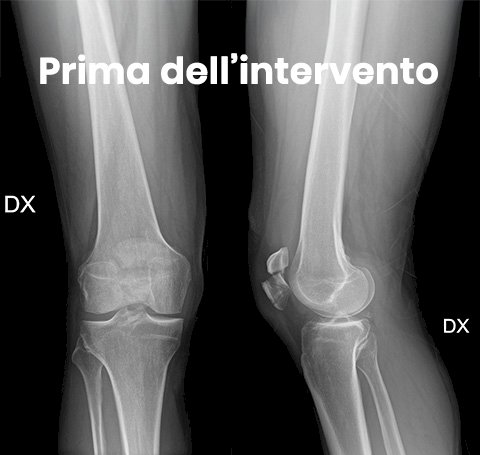

Le radiografie sono la tecnica diagnostica maggiormente utilizzata con proiezioni in antero posteriore e laterale del ginocchio ed in alcuni casi anche assiale della rotula. Nei casi dubbi in cui si sospetta la frattura della rotula ma le radiografie non sono in grado di evidenziarla perchè particolarmente composta si richiede una TAC per valutare la presenza della frattura. Raramente alle radiografie si possono riscontrare rotule bipartite ovvero la rotula presenta due parti che durante l'accrescimento osseo non si sono unite determinando quindi la presenza di due porzioni di rotula che possono essere scambiate per una frattura ma che attraverso l'esame obiettivo la clinica ed eventualmente una radiografia del ginocchio controlaterale si può capire che la rotula non è fratturata ma bipartita.

Se la frattura è scomposta ovvero i frammenti ossei si sono spostati facendo perdere l'anatomia normale della rotula sarà necessario intervenire chirurgicamente per ridurre la frattura quanto più anatomica possibile e fissarla in modo che non si scomponga durante il periodo della guarigione dell'osso. Infatti i tendini che si inseriscono sulla rotula potrebbero scomporre la frattura trazionandone i frammenti durante il movimento del ginocchio, quindi è necessario fissarla con dei mezzi di sintesi una volta ridotta mediante cerchiaggi metallici, viti o fili metallici.